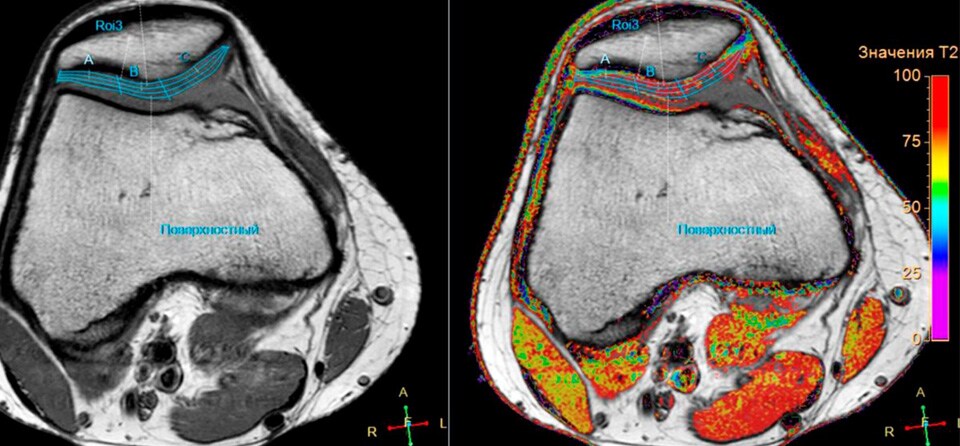

Цель Изучить релаксационные показатели Т2, Т1rho-картирования хрящевой ткани суставной поверхности коленного сустава, как количественный критерий выраженности патологий различного характера. Описание проекта Дегенеративные изменения суставов в зависимости от возраста, величины физической нагрузки, в том числе массы пациента, а также сопутствующих заболеваний приводят к изменениям биохимических процессов в хрящевой ткани. Стандартный МРТ протокол позволяет создать достаточный контраст для выявления морфологических изменений в гиалиновом хряще суставной поверхности. На данный момент самым распространенным методом оценки тяжести острых и хронических повреждений суставного хряща из-за своей простоты получили системы классификации, предложенные Outerbridge (1961), Jackson (1988) и Yulish B.S. et al. (1987). Такой подход крайне эффективен в оценке степени хондромоляции, однако не отражает нарушения биохимических изменений в выявленных очагах и зонах поражения гиалинового хряща. Значения релаксационных параметров Т2, Т1rho, получаемых методиками количественной МРТ (qMRI), связаны с физическими свойствами, а также с водным и коллагеновым составом внеклеточного матрикса хряща коленного сустава. Исследование изменения этих параметров при различных заболеваниях, травмах и иных факторах позволит построить точные биофизические модели повреждения хряща, а также потенциально разработать количественные методы определения стадии хондромоляции. Задачи Создание и оптимизация быстрых протоколов сканирования, а также процесса обработки таких изображений для получения Т2 и T1rho карт хрящевой ткани коленного сустава. Получение релаксационных показателей хрящевой ткани суставных поверхностей на примере коленного сустава, в зависимости от степени хондромаляции в разных группах пациентов.

Результаты Разработаны оптимальные протоколы сканирования для получения карт Т2 и Т1rho гиалиновой хрящевой ткани коленного сустава. Проведены измерения значений Т2 хрящевой ткани суставной поверхности коленного сустава у пациентов с рассекающим остеохондритом, а также влияние индекса массы тела на параметры Т2. Результаты представлены на конгрессах: РОРР 2019, Радиология 2018, Радиология 2017

Процесс получения T1rho карт.